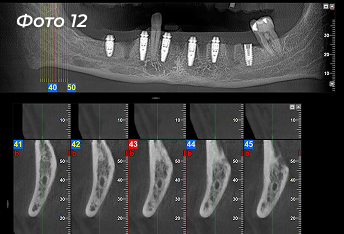

Через 4 месяца после первой операции было проведено оперативное вмешательство на нижней челюсти. Была выбрана другая тактика, были удалены сразу все зубы (Фото 11).  Установлено 6 имплантов  (Фото 12) по хирургическому шаблону  (Фото 13).